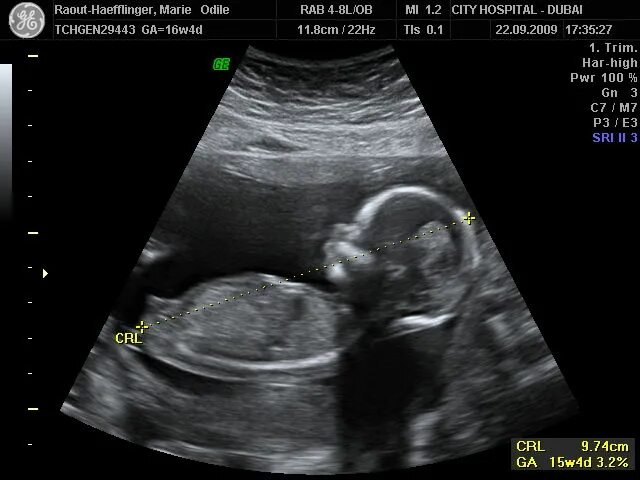

Ребенок в 13 недель